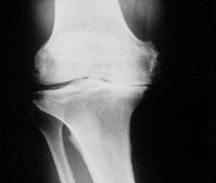

Arthrose

Arthrose ist eine durch Verschleiß bedingte Erkrankung des Gelenkknorpels, der das altersübliche Ausmaß übersteigt. Die Ursachen hierfür sind vielfältig (Genetik, Überlastung, Alter, Gewicht, Sport) und geht in der Regel mit einer schmerzhaften Entzündung der Gelenkschleimhaut einher (Arthritis).